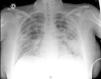

Exploración obstétrica normal. Se le realizó PCR de COVID-19 que resultó ser positiva. En la analítica destacaba: 20.900 leucocitos (98% de PMN), linfopenia 200, dímero D 578ng/ml, PCR 28mg/dl, LDH 223U/l y procalcitonina 5,33ng/ml. Desde el punto de vista respiratorio con unas cánulas nasales a 3l tenía una PO2 de 140mmHg. En la radiografía de tórax se apreciaban infiltrados pulmonares bilaterales multilobares con patrón intersticio-alveolar, con consolidaciones alveolares en el lóbulo superior izquierdo, pinzamiento de senos costofrénicos y engrosamiento cisural derecho por derrame pleural de leve cuantía (fig. 1).